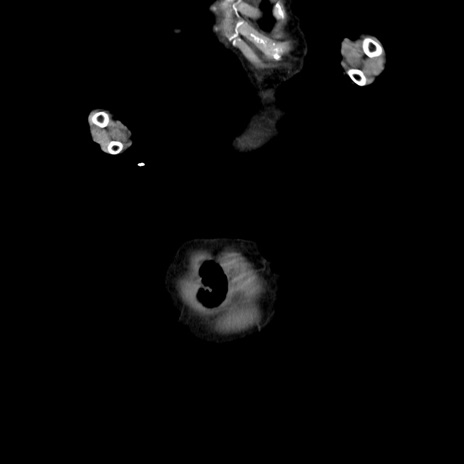

横断像